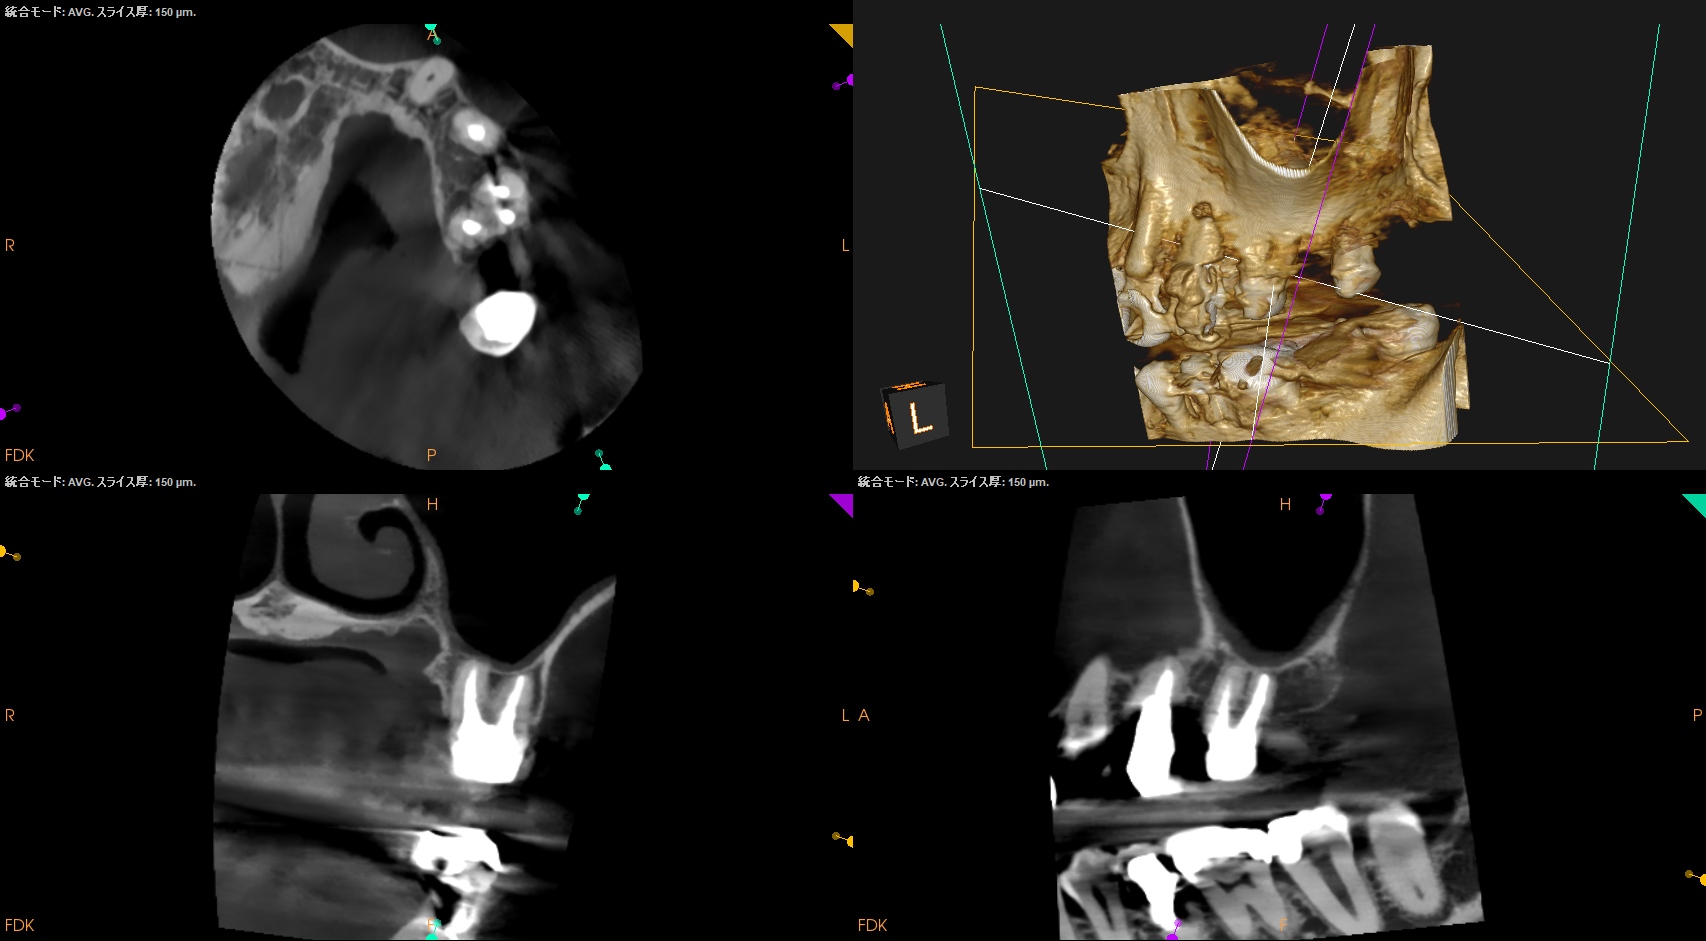

#3,14,16 Re-RCT 1yr recall(2025.10.20)

#3

MB

DB

P

#14

#16

初診時+治療直後と比較した。

劇的に病気が治癒している。

特に#16は凄まじい。

超音波洗浄しかできなかったのに根尖病変が治癒しているのだ。

免疫力が非常に強い患者さんなのだろう。